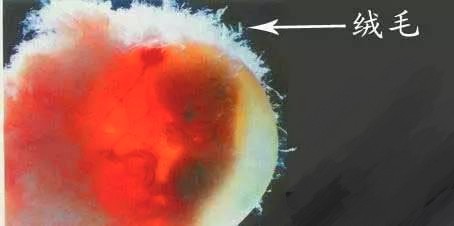

第二次排畸检查:妊娠10~12周绒毛活检;

①绒毛活检是一种产前检查,用来检测是否有如唐氏综合征那样的染色体异常疾病。这种检测就是从胎盘上的微小指状突起,也就是被称为绒毛的部分来获取细胞,并进行细胞遗传结构的分析。

②与羊水穿刺相比,绒毛活检的主要优势在于,可以在你怀孕的更早些时间进行。虽然有些医院是在怀孕13周做绒毛活检,但一般都是在怀孕11~12周来做。若是做羊水穿刺,则需要等到怀孕第15~18周时,也就是要到孕中期才能做。